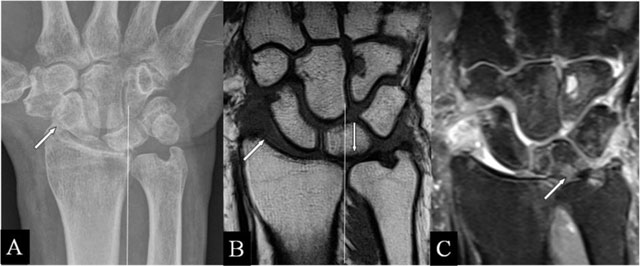

Radioscafoid abutment

Intra-articular fractures of the radius may heal with a residual step-off [6], seen on radiographs, CT, and MRI (Figure 1A–C). The radial deviation is limited. MRI illustrates the disappeared cartilage (Figure 1A and B) or the surface disruption (Figure 1C). In radial deviation (Figure 1B), bumping of the scaphoid against the prominent radial fossa zone causes repetitive impaction, resulting in BMO.

Figure 1

Radioscafoid and radiolunate abutment. (A) Coronal SE T1-WI; (B, C) Coronal 3D-GRE; (D, E) PA plain radiographs; and (F) Coronal SE PD-WI FS. (A) Sequela of an intra-articular fracture of the distal radial epiphysis with a residual step-off (oblique arrow) and marrow oedema (vertical arrow) at the proximal pole of the scaphoid bone. (B) Centrally, the cartilage is destroyed and the radial deviation is blocked. (C) Cartilage step-off in another patient. (D) The parasagittal intra-articular fracture was initially missed. (E) Consolidation with a depressed part of the articular surface. (F) Radiolunate abutment with blocked ulnar deviation.

Radiolunate abutment

Lunate bone impaction on its articular fossa may cause SAS. Parasagittal radial fractures (Figure 1D) need careful follow-up by radiographs or CT [6] in order to detect displacements, possibly causing SAS (Figure 1E and F) and limiting the ulnar deviation (Figure 1F).